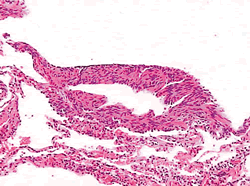

刘鸿瑞教授(病理科):肺活检标本肉眼见肺膜表面多个隆起,直径0.1~0.2 cm,切面见肺为多囊状,直径0.1~0.5 cm,囊内壁光滑。镜下(图3)见肺组织呈囊状,可见部分正常肺泡及扩张肺泡,肺泡间隔有丰富的梭形、长核、胞浆丰富的平滑肌样的细胞。免疫组化示LAM的标记抗体HMB45(+)(图4),PR(+),ER(-)。病理特征符合LAM,可确诊。

图3 肺组织病理显示扩张的淋巴管及异常增生的平滑肌